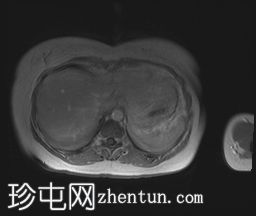

轴位T2加权像

脂肪抑制像

冠状位T2加权像

可见膀胱左侧壁有一边界清晰的T2低信号实

性病

灶,无扩散受限,均匀强化。未见膀胱周围侵犯或肾积水。

子宫底部前壁可见一小肌瘤。双侧卵巢可见无强化囊肿。盆腔及腹股沟未见异常淋巴结肿大。

这是一例经组织学证实的膀胱平滑肌瘤病例。